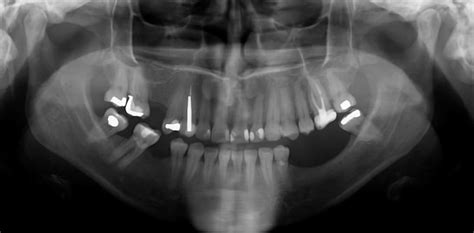

- Revisiones dentales regulares: Reconocer los primeros síntomas es clave para detener el progreso de este problema. Si sospechas que estás experimentando pérdida ósea, no dudes en acudir a tu dentista para una evaluación. Una buena planificación mediante la realización de un buen estudio a través de la obtención de imágenes 3D con los escáneres CT de haz cónico, permite ver los dientes, los maxilares y las estructuras relacionadas en una vista completa de 360º. Cuando los huesos pierden densidad, se vuelven más porosos. La baja densidad del hueso alveolar se puede detectar con anticipación mediante la captura de imágenes 3D con los escáneres CT de haz cónico. Cuanto más blanco es el color del hueso en la radiografía, más denso es.